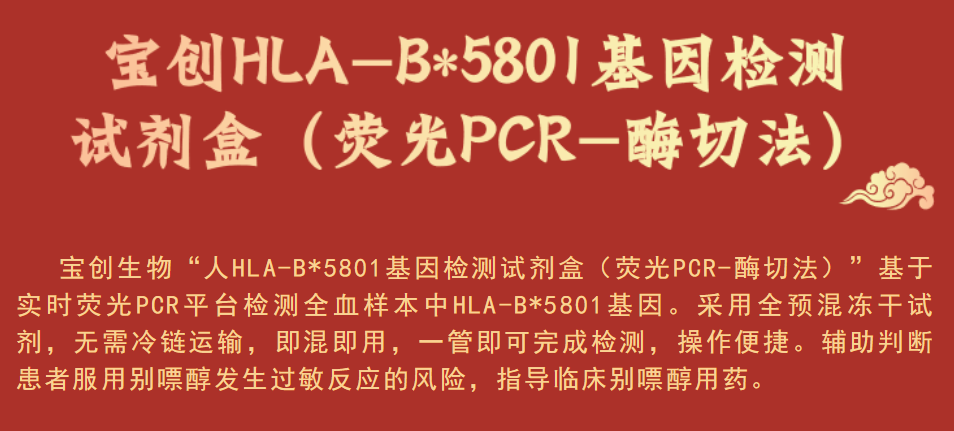

е…Ӣж—Ҙ�пјҢ�пјҢ�пјҢе®қ马bm1122зәҝи·ҜйЎ¶зә§з”ҹзү©пјҚдәәHLA-B*5801еҹәеӣ жЈҖжөӢиҜ•еүӮзӣ’пјҲиҚ§е…үPCR-й…¶еҲҮжі•пјүжӯЈејҸиҺ·еҫ—еӣҪ家иҚҜе“Ғзӣ‘и§ҶжІ»зҗҶеұҖпјҲNMPAпјүжҸӯжҷ“IIIзұ»еҢ»з–—еҷЁжў°жіЁеҶҢиҜҒпјҲжіЁеҶҢиҜҒеҸ·пјҡеӣҪжў°жіЁеҮҶ20233401644пјү�гҖӮ�гҖӮгҖӮгҖӮ